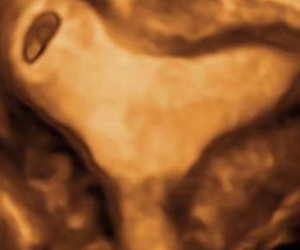

How To Do Agosto 2021: Cesarean Scar Pregnancy

Cari soci, questo mese un nuovo video "How to do", sulla diagnosi ecografica di gravidanza su cicatrice di pregresso taglio...